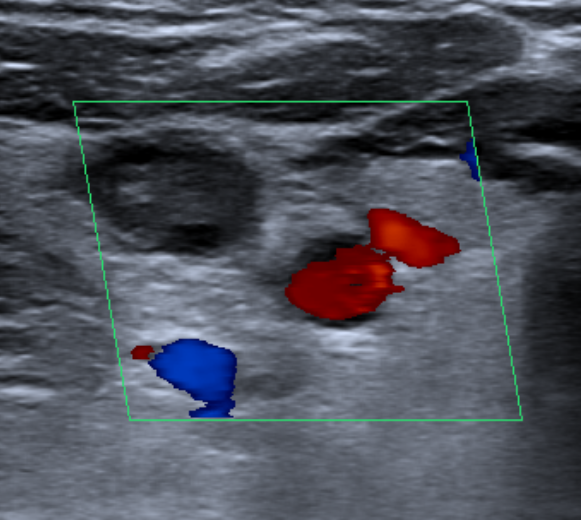

Thrombophilia studies revealed Hyperhomocysteinemia of 17.2 μmol/L (normal values 3.0 - 15.0), Total Protein S 54.1 % (normal values 65.0 - 140.0), and weak positiveness of a lupic anticoagulant. Six months after the episode, all parameters were normalized. Doppler ecography was done, in which an incidental jugular vein thrombosis was discovered (Figure 3 & 4).

Figure 3 Doppler December 2018: Incidental right jugular vein thrombosis.

Figure 4 Right sublcavia, left yugular and left subclavia veins were permeable.